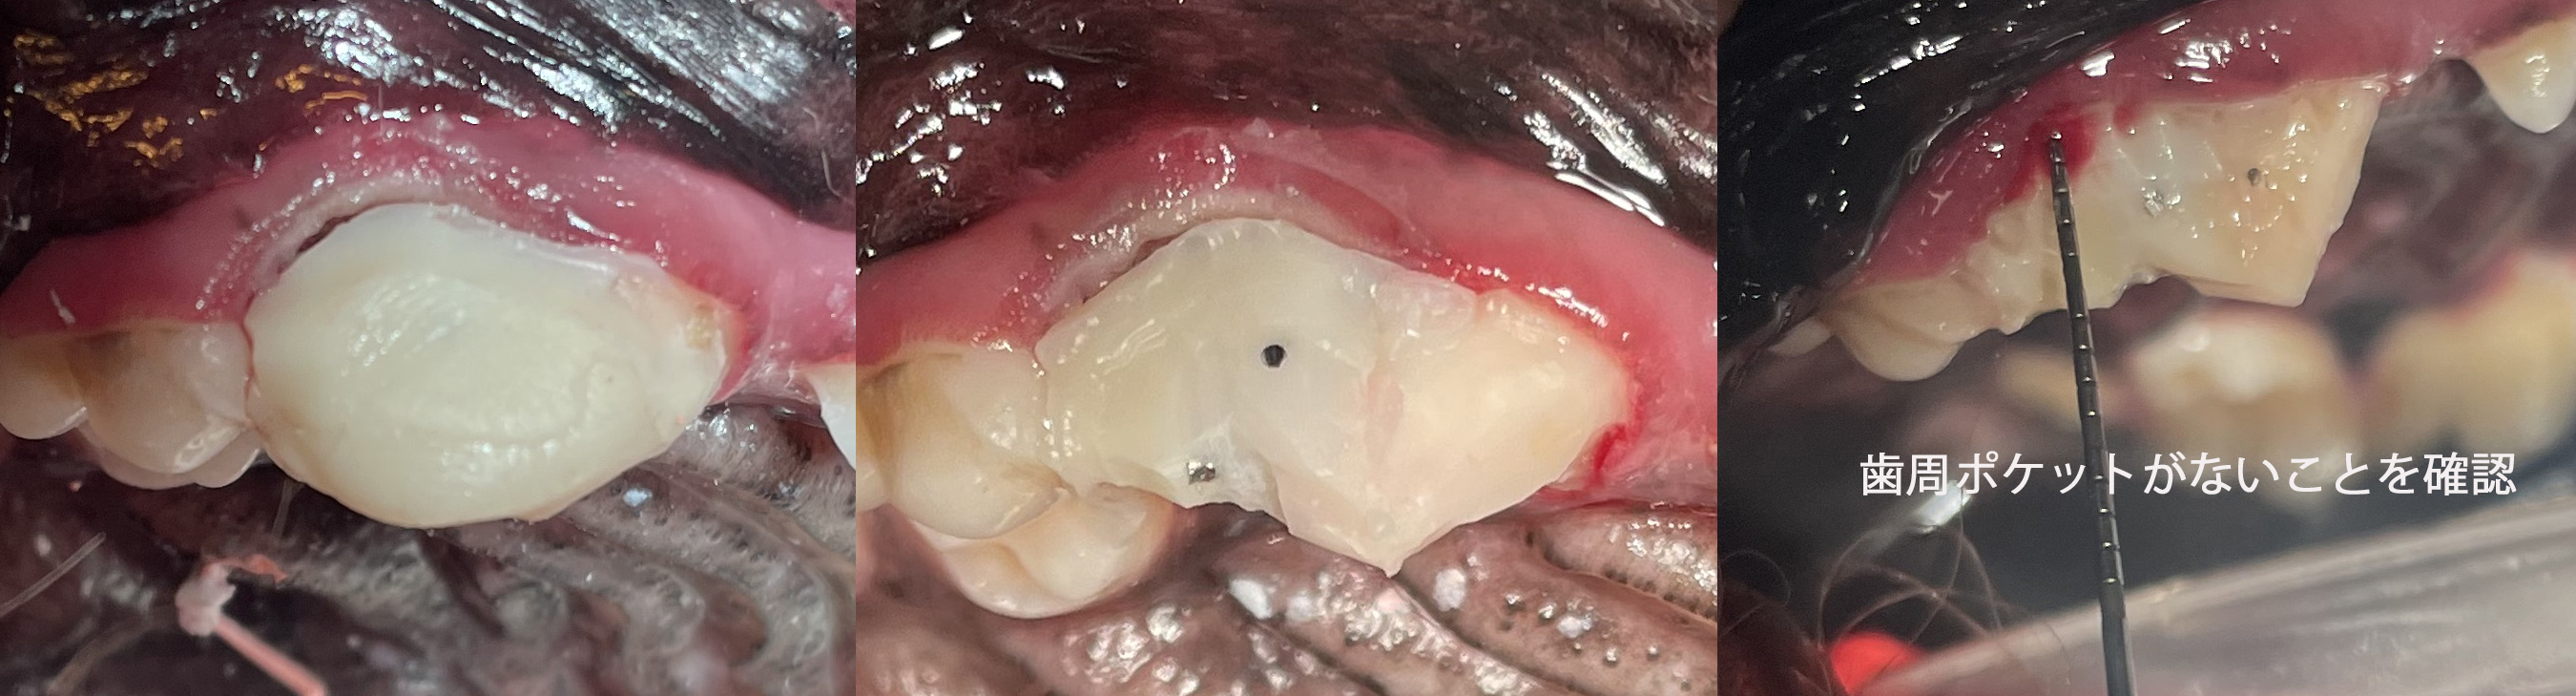

● 歯の破折 4 : 切 歯 の 破 折

真ん中の歯が折れています。

折れた部分を黄色でトレースしています。

![]()